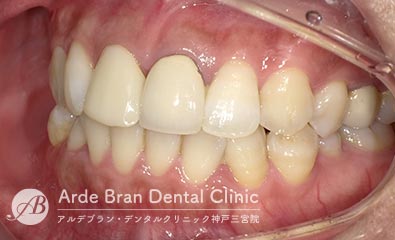

- ジルコニアセラミッククラウン(20代 女性 治療期間1カ月)

- 他院で入れた前歯の被せ物の形態や色調が隣の歯と合っていないため、やり替えたいとの事でご来院されました。切端に透明感があり、歯頚部から歯冠部にかけてグラデーションがある難しい歯でしたがトップテクニシャンとの連携により見事に再現する事が出来ました。

- 治療前

- 治療後

| 治療方法 | ジルコニアセラミッククラウンによる審美歯科治療 |

|---|---|

| 治療本数 | 2本 |

| 治療期間(通院回数) | 1カ月(4回) |

| 費用 | ジルコニアセラミッククラウン 24万円+TAX 仮歯 6千円+TAX |

| リスク副作用 | 審美歯科治療に関するリスクや副作用について、詳しくはこちらをご参照ください。 |